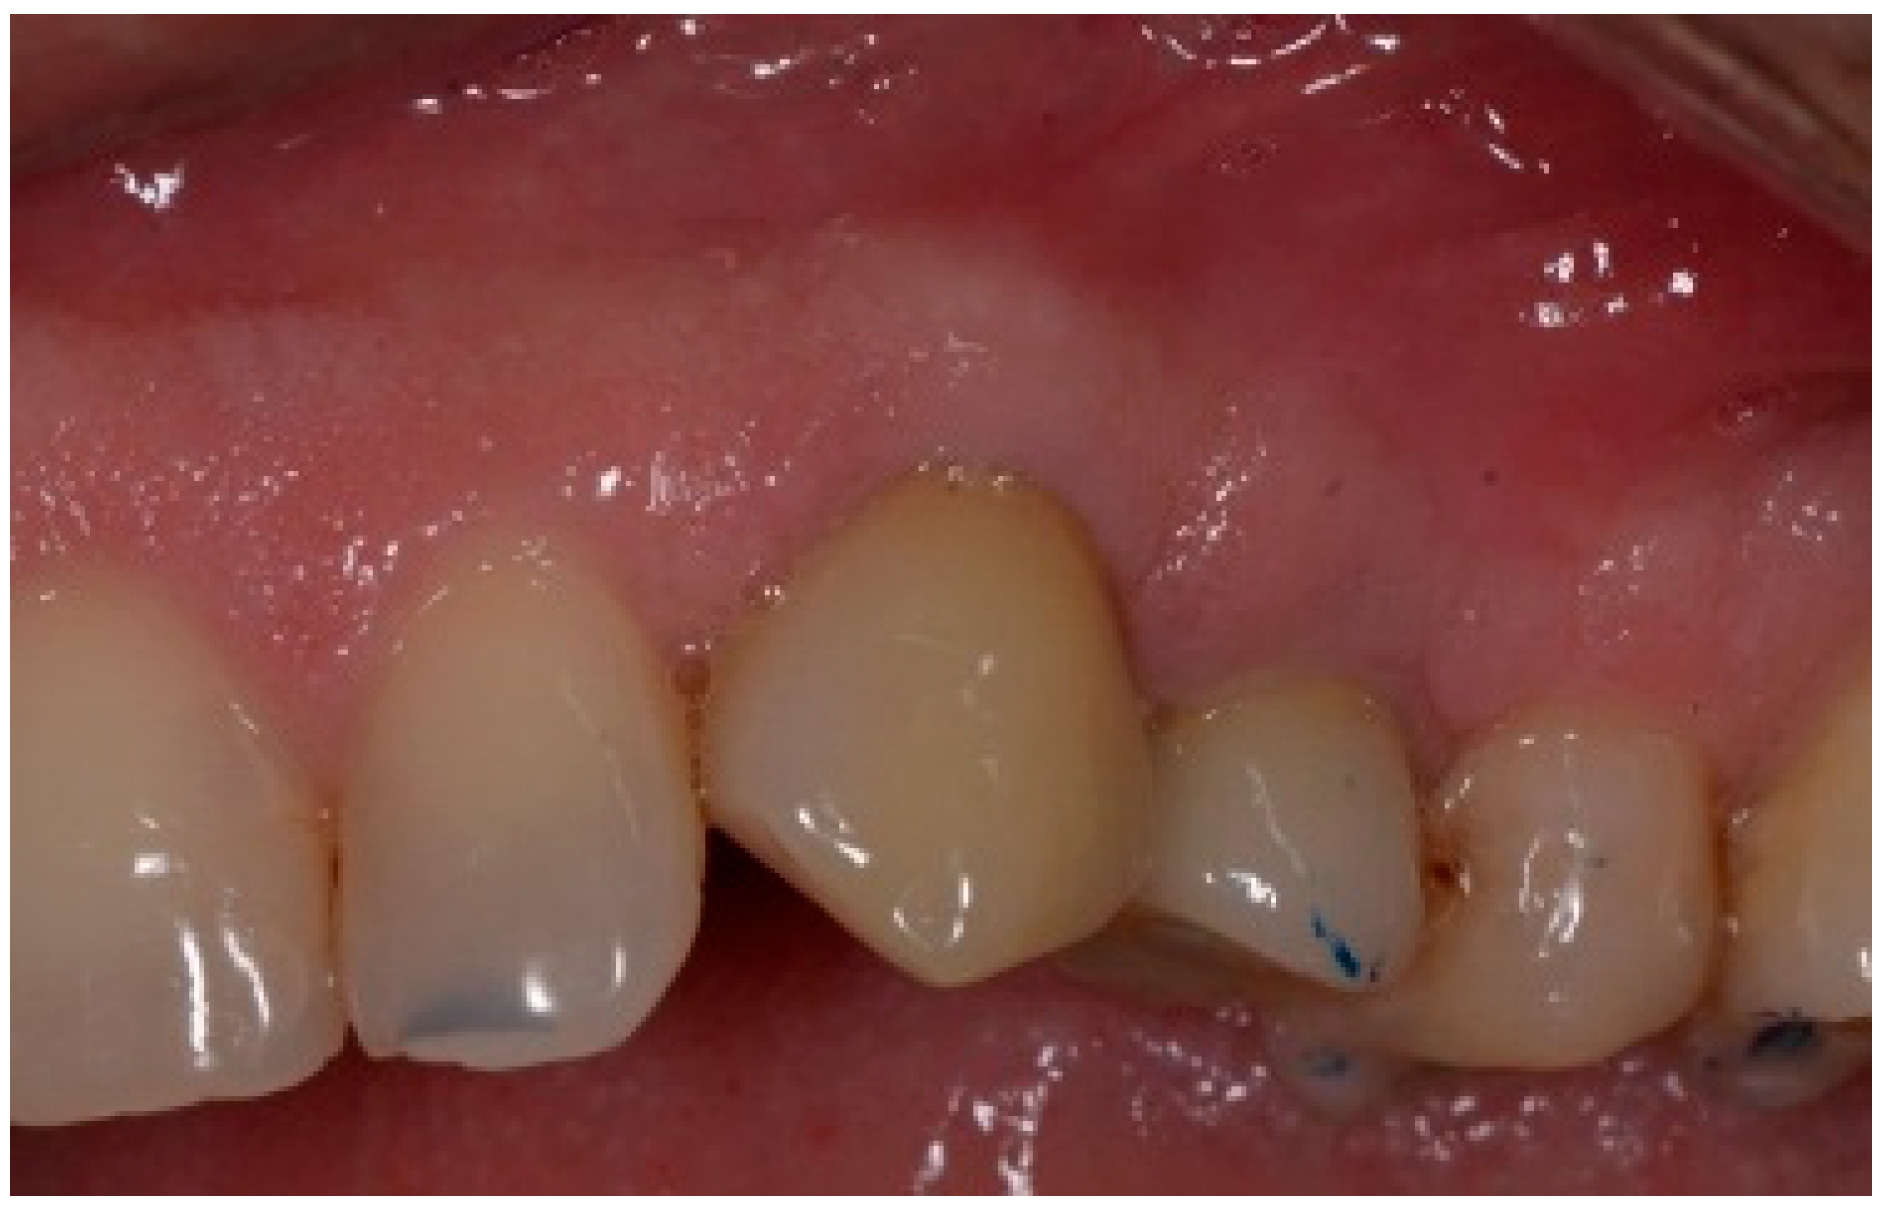

5. Patient 4

A 51-year-old male patient in good health and a non-smoker presented with a fractured maxillary canine with recurrent subgingival caries, and a failing root canal on the maxillary first premolar (Figure 18). The treatment plan consisted of the extraction of both teeth #11 and #12 roots, followed by the placement of implants. The preoperative surgical protocol described in patient 1 was followed. Figure 19 represents the residual boney defect associated with this area after implant placement. Similar to the previous cases, graft material was placed, and the area was closed for healing. Chairside temporary crowns were fabricated, followed by the placement of zirconia crowns in six months. Figure 20 represents the area three years after treatment.

Figure 18.

Clinical view of fractured tooth #11 and existing crown on tooth #12.